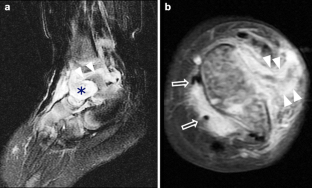

Synovium is the thin membranous lining of a joint. It produces synovial fluid, which lubricates and nourishes the cartilage and bone in the joint capsule. Synovial diseases in children can be classified as normal structures as potential sources of pathology (synovial folds: plicae, infrapatellar fat pad clefts), noninfectious synovial proliferation (juvenile idiopathic arthritis, hemophilic arthropathy, lipoma arborescens, synovial osteochondromatosis, pigmented villonodular synovitis, reactive synovitis), infectious synovial proliferation (pyogenic arthritis, tuberculous arthritis), deposition disease (gouty arthropathy), vascular malformation, malignancy (metastasis) and intra-/periarticular cysts and cyst-like structures. Other intra-articular neoplasms, such as intra-articular synovial sarcoma, can mimic synovial disease in children.

Fig. 3